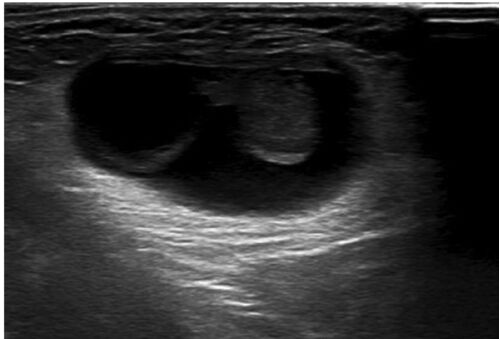

症例66:片側大陰唇が腫脹した6週女児(Ann Emerg Med. 2020 Dec;76(6):e123-e124.)

病歴/身体所見 ・6週女児 ・片側陰唇腫大のためER受診 ・特記すべき既往はない ・左大陰唇に2cmほどの押しても縮小しない腫瘤を認めた ・バイタルサインに異常はなし 検査 ・陰唇の超音波検査が実施された 1.5cmほどの構造物(卵巣)と水腫を認める 卵巣の血…